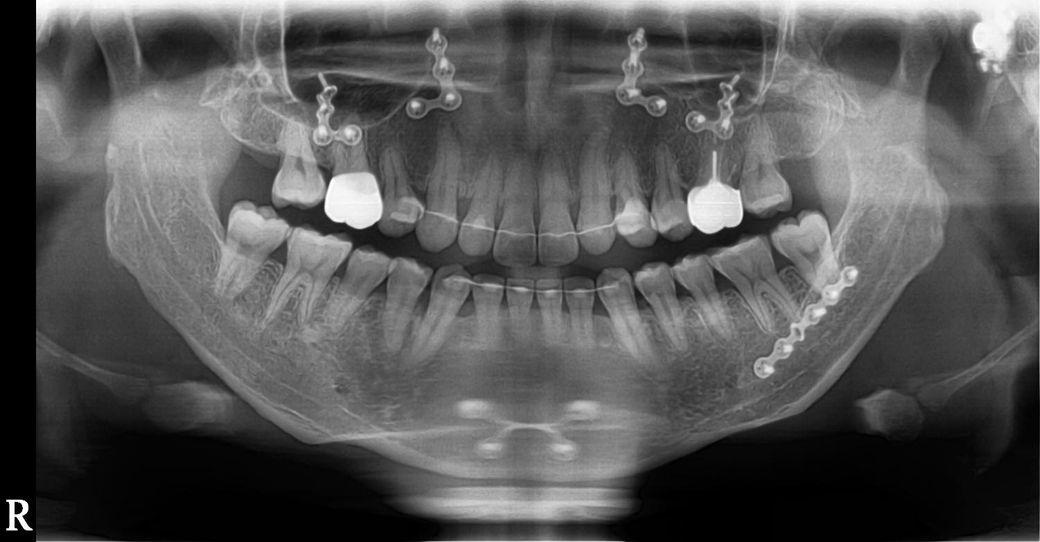

치아사진 분석좀 해주세요(사진첨부)

상악 우측송곳니(사진은좌측)

철사가있을때와 반제거했을때 비교

철사가있을때 이미 벌어져있던건지 아니면 제거후 벌어진건지 진문가소견좀 주세요

사진확대하면 잘보입니다

• 2번 째 사진

철사가있을때 이미 벌어져있던 부분이 보입니다. 위 사진만으로 명확한 판단은 힘듭니다.

상악우측 송곳니 살짝 이동은 있어보입니다 다만 정확히 비교하려면 다른 기록(캐스트, 치근단 엑스레이사진) 필요합니다

엑스레이 사진만으로는 해당치아가 이동했는 지여부를 정확하게 파악하기 힘듭니다. 사진을 찍을때 미세한 각도의 차이로 인해서 치아의 위치를 판단하기가 힘들기 때문입니다.